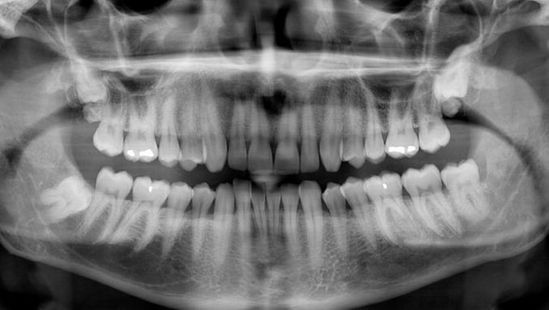

2. Skaitmeninė panoraminė rentgeno nuotrauka (ortopantomograma).

Ji atliekama:

• Sudarant burnos ertmės gydymo planą.

• Esant daugybiniams dantų pažeidimams.

• Esant sudėtingiems dantų rovimams ( protiniai, retinuoti dantys).

• Prieš didesnės apimties protezavimą.

• Prieš ortodontinį gydymą (tinka įvairaus amžiaus pacientams).

• Prieš implantaciją ar kitą chirurginę intervenciją.

• Norint įvertinti kaulo būklę apie dantis (sergant paradontoze arba jos prevencijai).

• Tinka paciento ištyrimui net ir tais atvejais, kai jis negali pilnai išsižioti.